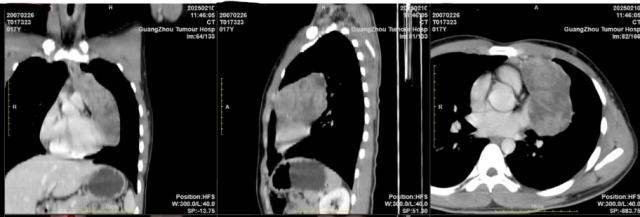

17岁的男孩小圆(化名)近段时间常常感到胸闷,运动后加重,气喘不止。父母察觉异常后带他去医院检查,竟发现前纵隔内藏着一个直径15厘米、足有柚子大小的巨瘤,紧紧贴住心包与心脏前壁。他们迅速带着小圆来到了广州医科大学附属肿瘤医院寻求帮助。

该院胸外科学科带头人赵健教授接诊后,组织了MDT多学科专家进行会诊。“经过病理检查,患者患的是低度恶性的胸腺瘤。这类肿瘤对放化疗不敏感,手术是更好根治的手段。”赵健教授解释,低度恶性肿瘤虽转移风险较低,但若切除不彻底,仍可能局部复发,“尤其对于年轻患者,必须确保根治性切除,避免二次手术的风险。”

然而,在选择手术方案时,小圆的父母却提出了“微创手术”的诉求。“传统开胸手术需劈开胸骨,如此巨大的肿瘤,预计切口长达35厘米,大面积的术后瘢痕,对青少年心理影响大。”

为此,赵健团队评估起使用机器人辅助手术的可能性。“机器人手术通过控制台的精确操作,机械臂能实现亚毫米级的移动,精准度与稳定性更高,通常只需3-4个直径0.8-1.2厘米的操作孔,相比开放手术大幅减少组织损伤,患者恢复快。”赵健团队表示,但此前很少有如此巨大肿瘤的成功案例,“微创的前提是保证安全切除、彻底性,不能为了微创而微创。”

经过严密的分析讨论,考虑肿瘤生长的部位有通过机器人手术根治的机会,赵健团队最终决定尝试达芬奇机器人辅助微创手术,同时也做好了后备预案:“我们反复与家属沟通,强调若术中无法切除,也要做好中途转为开胸手术的准备。”

手术当天,机械臂通过4个“钥匙孔”精准进入胸腔,在3D镜头的高清视野下,巨大肿瘤得以完整分离,后扩大其中一个切口至3厘米取出。“若直接开刀,创口可能是现在的10倍。”最终手术成功。赵健强调,低度恶性胸腺瘤复发率较低,但仍需长期随访,“每半年一次的检查必不可少。”